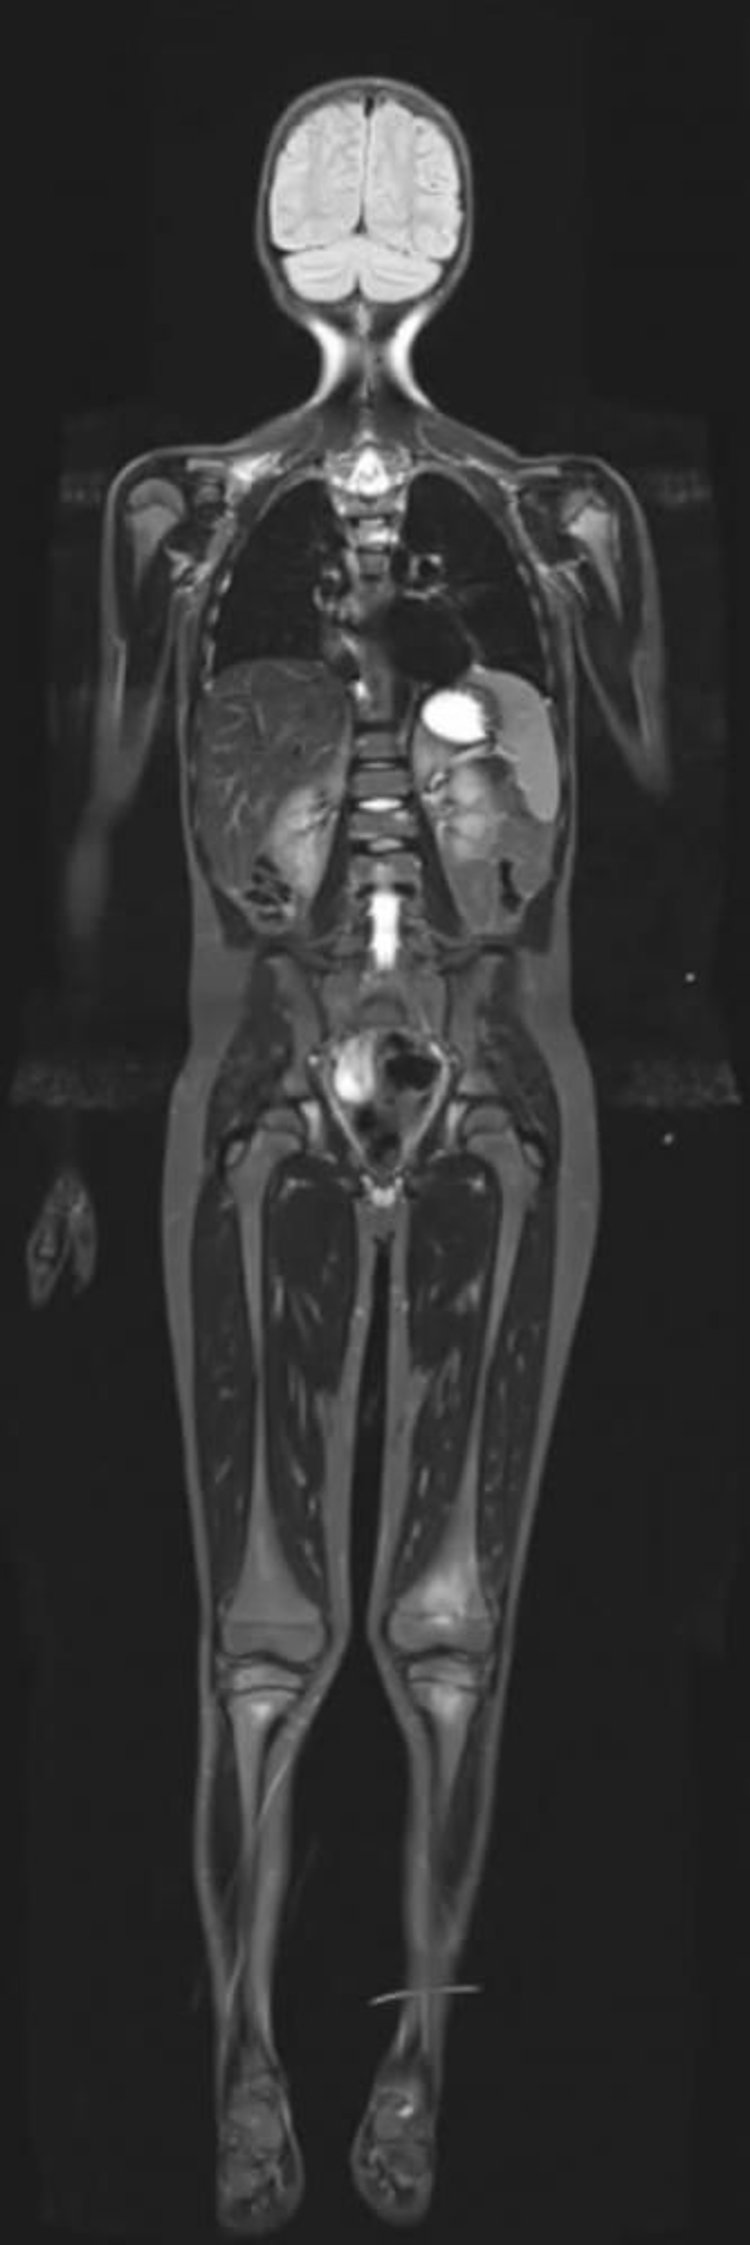

MRI phục hồi đảo ngược T1 ngắn của toàn bộ cơ thể

MRI phục hồi đảo ngược T1 ngắn có thể ngăn chặn tín hiệu từ chất béo cho phép tăng bắt thuốc cản quang ở các mô khác có lượng nước cao.

Hình ảnh do bác sĩ Hakan Ilaslan cung cấp.